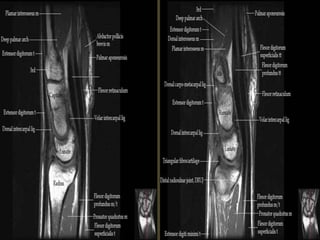

MR Sequences images.

T1WI

T21WI (Upper Egypt).

Wrist X-ray Anatomy.

Pronator quadratus.

The transverse carpal ligament (short arrows) extends from the hook of the hamate (long

arrow) to the tubercle of the trapezium (arrowhead), forming the floor of the carpal tunnel.

At the radial aspect of the carpal tunnel, the flexor digitorum tendons are arranged in two

rows (separated by dotted line), the profundus tendons deep to the superficialis tendons. The

flexor pollicis longus tendon (star) is positioned at the ulnar aspect of the tunnel, separated

from the flexor carpi radialis tendon (curved arrow) by a ligamentous reflection of the

transverse carpal ligament. The median nerve is indicated (asterisk). - See more at:

http://radsource.us/palmar-bursae-and-flexor-tendon-sheaths/#sthash.mSFX1u0c.dpuf